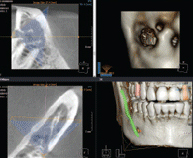

시작부터 다르다!

3차원 정밀진단 시스템

얼굴 골격을 빠짐없이 분석합니다

얼굴 골격의 모든 방향을 빠짐없이 촬영하고

치아와 치조골의 상태 및 잇몸뼈의 양과 길이 등의

전반적인 상태를 정확하게 측정하고 진단하여

한치의 오차 없는 시술로 진료의 안정성을 높힙니다.